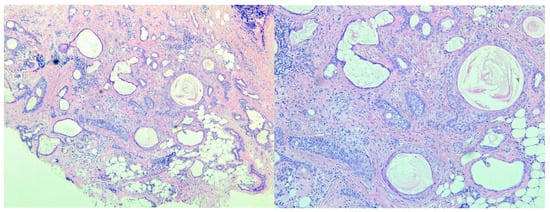

3. Histopathologic Assessment